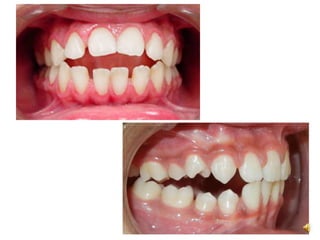

Overjet

• Horizontal relationship of the upper

teeth to the lower teeht in centric

occlusion

Overbite

• Vertical relation of the upper teeth to

lower teeth in centric occlusion

Importance

• Prevent soft tissue biting

• Guid the mandible through various

lateral movement

Overjet • Horizontal relationshipof the upper teeth to the lower teeht in centric occlusion Overbite • Vertical relation of the upper teeth to lower teeth in centric occlusion Importance • Prevent soft tissue biting • Guid the mandible through various lateral movement